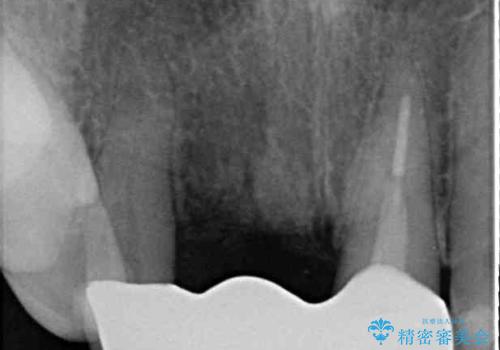

- 神経の抜いた歯が折れてしまい、痛みを感じて来院された患者様です。

折れてしまった歯は抜歯せざるを得ないため、抜歯と同時に仮歯を装着し、その後オールセラミックブリッジにて補綴することとしました。

折れた前歯を抜歯すると、歯肉が痩せてしまい、ブリッジの形態の審美性が失われることがあります。仮歯を調整することで審美回復が必要であるか判断しますが、今回は歯肉移植を行うことなく補綴治療を行いました。